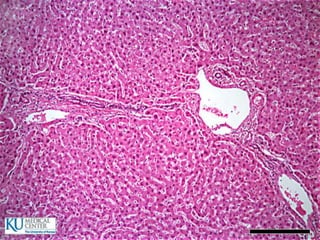

ESTÓMAGO

 2 a 3 L

 Esfínter esofagogástrico o cardias

 Esfínter pilórico

 Pliegues o arrugas longitudinales

Otras capas del estómago

 Submucosa

 Muscular

 Serosa